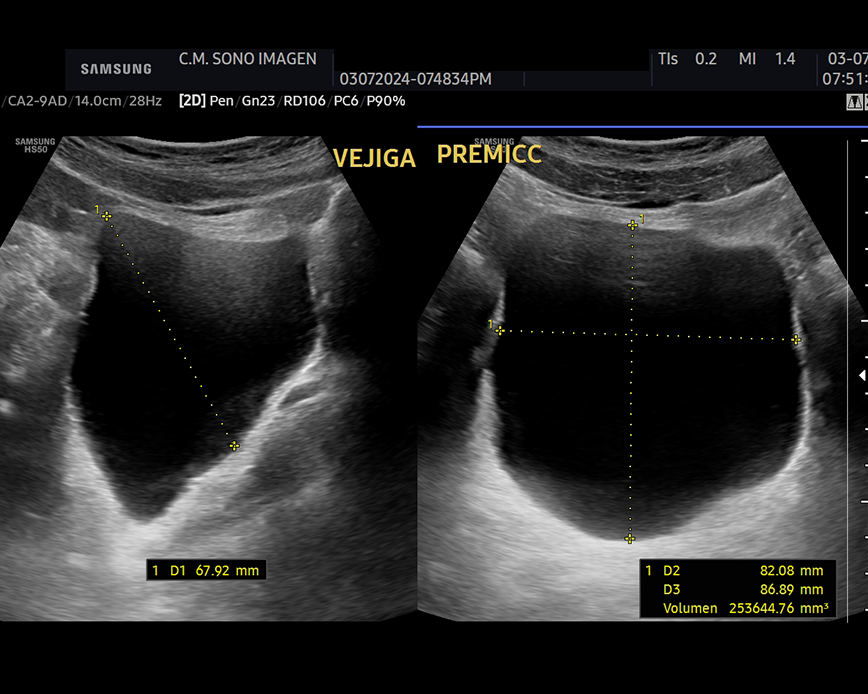

Ecografía Prostática

- hiperplasia prostática benigna(HPB)

- dificultad para orinar o retención urinaria